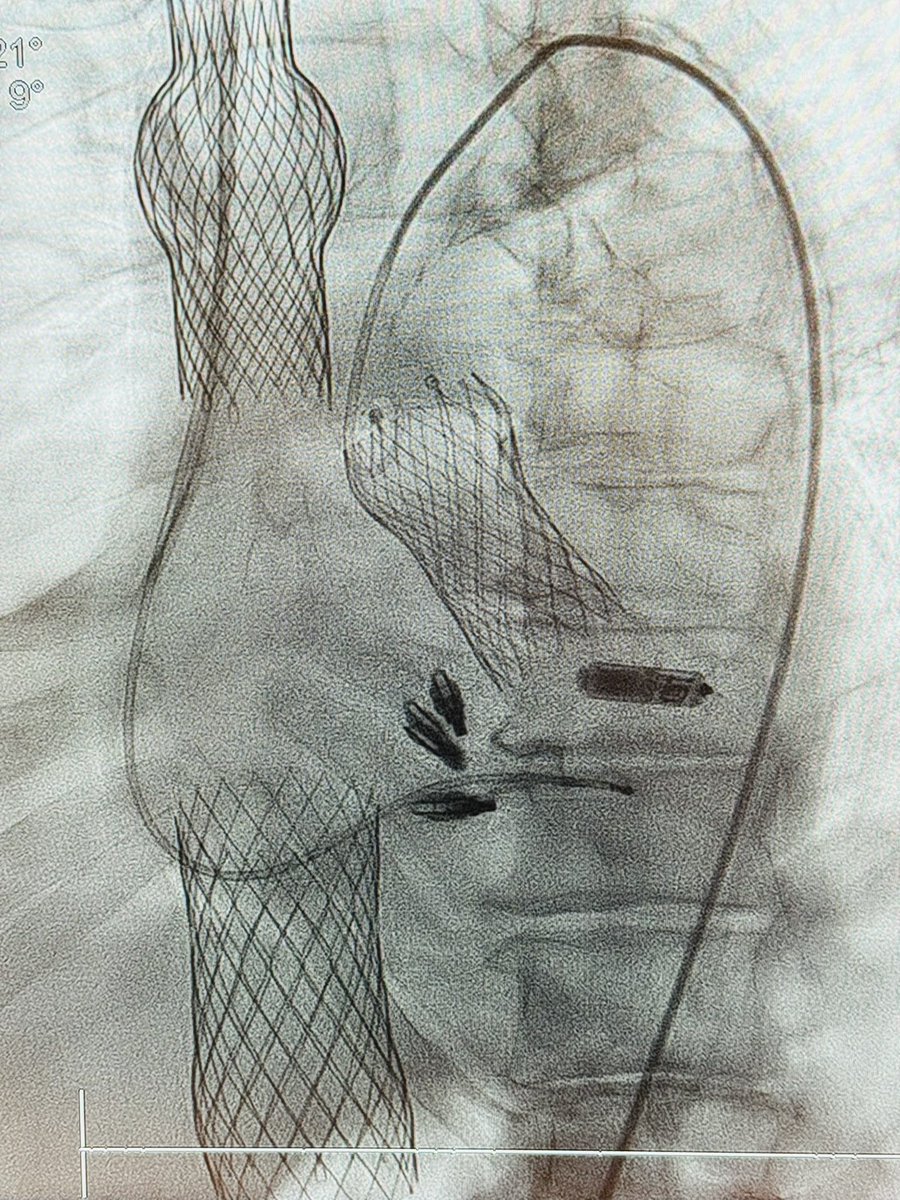

Good saturday night case - young pt, aortic valve endocarditis refractory cardiogenic shock. Transcaval ICE-guided LAVA-ECMO without pre- contrast CT. Full cardiocirculatory support with LV venting w only peripheral venous access. Thanks to Pedro Villablanca MD, MSc, FACC, FSCAI @HFHCardioFellow